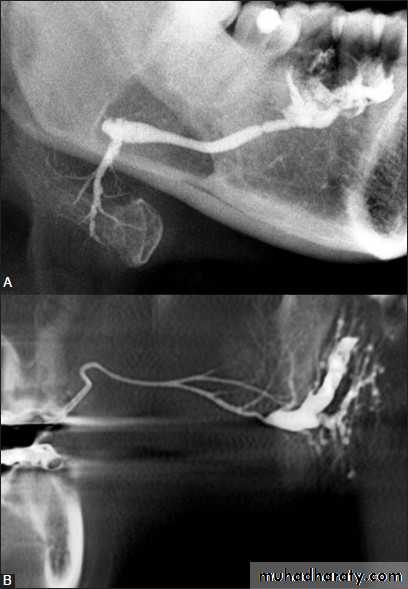

Sialography

1. Radiographs: OPG, Posteroanterior, True lateral, oblique lateral of mandible or intraoral occlusal views shows the calcified stone.2. Sialography: reveals dilation of the duct and site of the stone even if it is un calcified (radiolucent).

2. Sialogram: demonstrates the cavity defects which are filled with radiopaque contrast media, producing the “snow storm" appearance.

1. Sialogram: As the neoplasm enlarges it displaces the glandular tissue and its duct system to the periphery producing "grasping fingers" appearance in sialogram.2. CT scan, MRI & USG